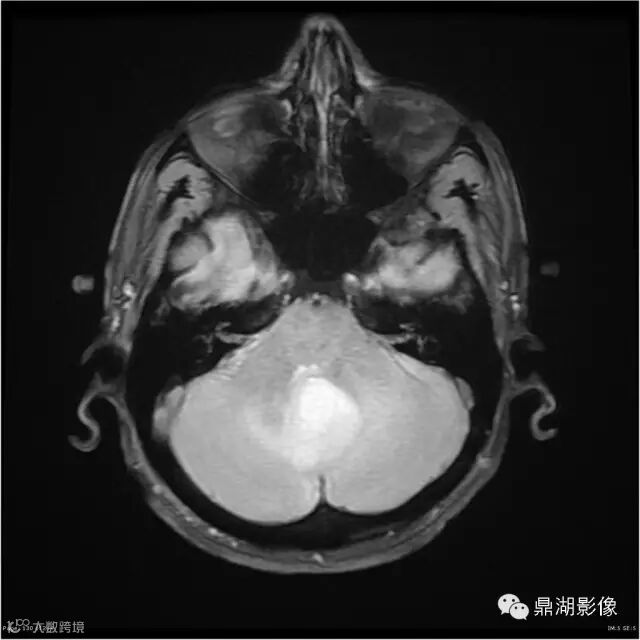

影像:可见一个约43 x 36 x 31mm的从小脑蚓部延伸而来的占位,T1WI、T2WI呈高低混杂信号,病灶周边见流空血管影及水肿带,增强病灶明显强化,中心见无明显坏死区,它紧靠左小脑幕上。第四脑室受压变窄,室管膜水肿,可见脑桥及延脑扁桃体进入枕骨大孔。

本例为一例实质性血管母细胞瘤。实性血管母细胞瘤CT平扫示病灶呈等或高密度,增强后可见明显强化。MRI平扫通常病灶很不均质,T1呈稍低信号为主的较混杂信号,T2呈等、高信号,DWI通常呈低信号或等信号。文献报道,实性血管母细胞瘤较典型的表现为瘤内及瘤周扩张的流空血管影,瘤周中、重度水肿。因此,小脑半球区的单发肿块伴流空血管影,周围大片水肿以及增强后肿块明显强化"形态规则"边界清楚,此时应将实性血管母细胞瘤考虑在内。